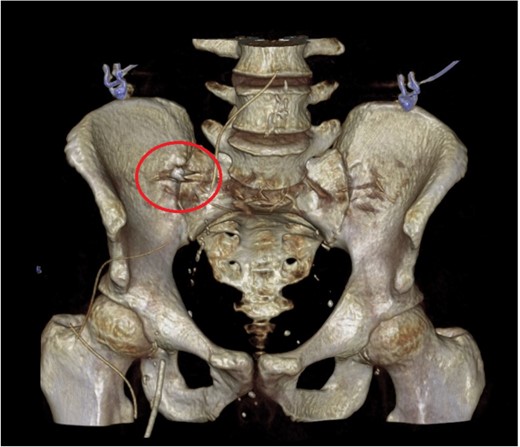

The patient proceeded immediately for a laparotomy. Intra-operative findings were of perforated appendicitis with four-quadrant purulent peritonitis. The caecum was healthy and an appendicectomy was performed. On examination of the appendix specimen, there was a perforation in the mid-point and a firm foreign body causing luminal obstruction at the base. On opening the specimen, the foreign body was identified as a decaying tooth containing a metallic filling (Fig. 3).

Specimen photograph of the retrieved tooth containing a metallic filling.